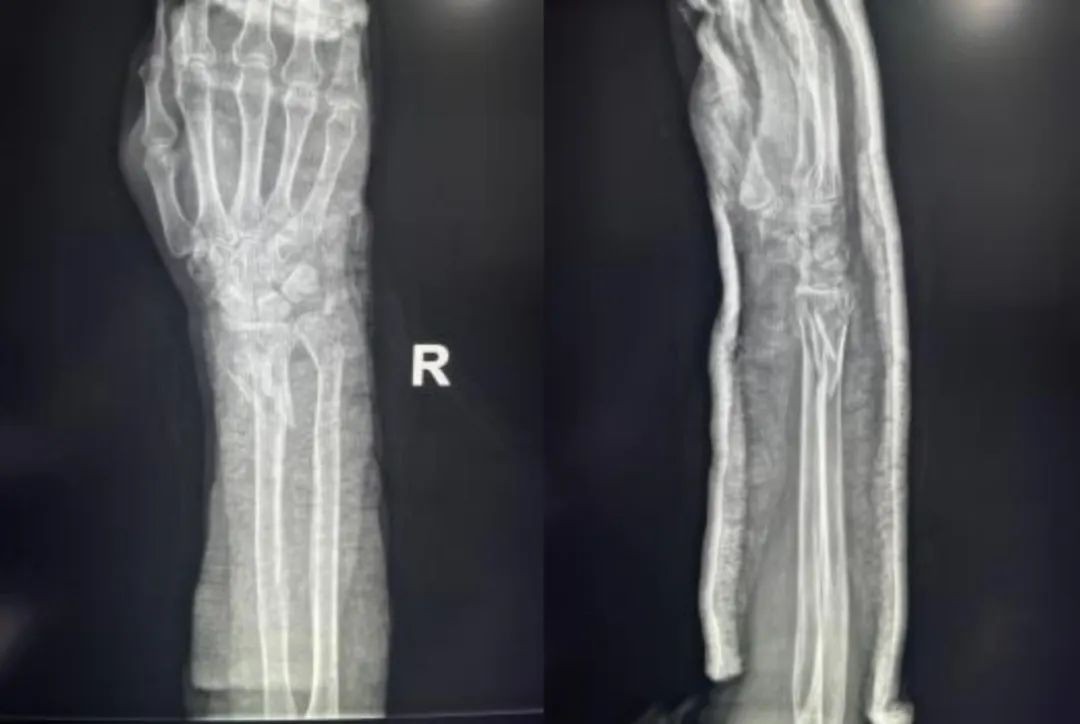

Случай ③